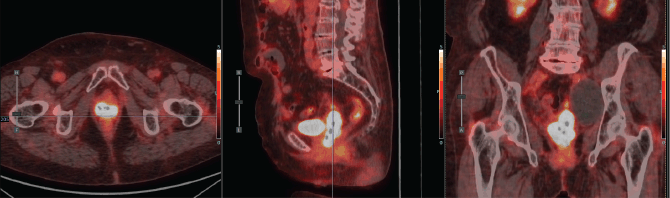

Figure 6. Case 2. PET-CT scan prior to BT. Axial, sagittal and coronal section. A hypermetabolic tumour mass in the vaginal vault and a left pelvic lymphocele were observed.

Figure 7. Case 2. Dose-volume histogram and dosimetric distribution of fraction #1 in axial, coronal and sagittal planes. It is shown in red CTV-HR, in orange CTV-IR, in light blue the rectum, in yellow the bladder and in purple the sigmoid colon.

Total dose was 8.2 Gy × 3 fractions, equating to roughly 48.1 Gy EQD24.5. The plan accounted for prior EBRT (30 Gy in 10 fractions). Although the bladder, rectum and sigmoid colon had some overlap with the new target volume, no dose-limiting constraints were exceeded (Table 1).